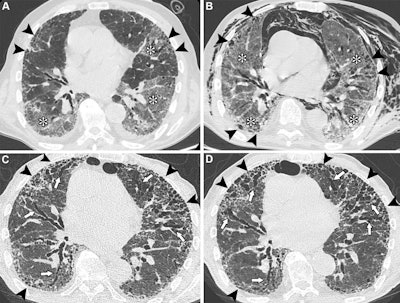

Unenhanced axial CT images show COVID-19 pneumonia in an 83-year-old male patient with preexisting interstitial lung disease (ILD). (A) Image shows ground-glass opacities in the lower lobes and in the lingula (*). Irregular reticular opacities with mild distal traction bronchiectasis are evident in the subpleural regions of both upper lobes (arrowheads), suggesting preexisting ILD with a probable usual interstitial pneumonia pattern. (B) Image obtained during hospitalization for respiratory distress shows spontaneous pneumomediastinum and diffuse chest wall subcutaneous emphysema, predominantly on the left side. The image also shows persistent, diffuse ground-glass opacities (*) and peripheral fibrotic lung changes (arrowheads). (C) Unenhanced follow-up image obtained at six months shows the progressive nature of lung fibrosis, with the development of honeycombing (arrowheads) and severe bronchiectasis (arrows), predominantly affecting the anterior peripheral regions of both lungs. (D) Unenhanced follow-up image obtained at 14 months shows the progression of honeycombing (arrowheads) and severe bronchiectasis (arrows) at the anterior peripheral regions of both lungs. In this case, SARS-CoV-2 infection likely acted as a trigger for the exacerbation of previously undiagnosed fibrotic ILD, with mechanical ventilation potentially contributing to extensive fibrosis in the anterior lung regions (arrowheads). The patient was administered antifibrotic therapy after the resolution of the acute phase.RSNA